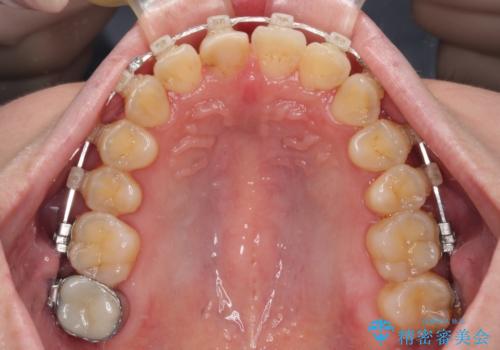

- 矯正装置

- クリアブラケット

- 治療期間

- 2年4ヶ月

- 治療回数

- 30回以上